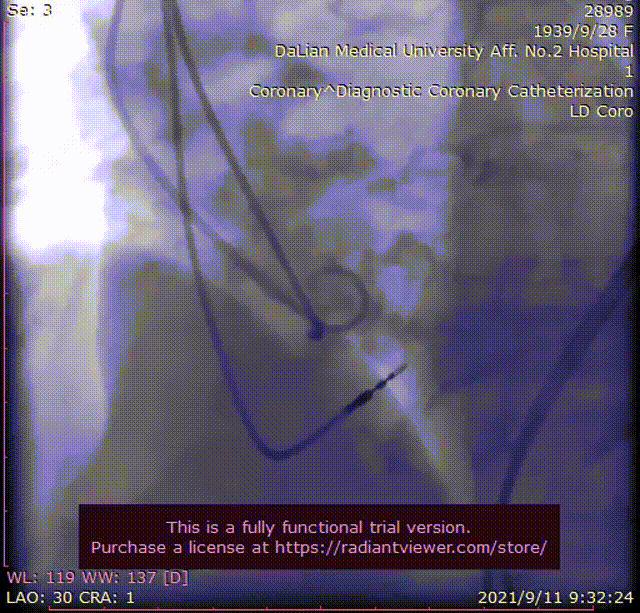

术中影像

主动脉根部造影

RCA造影

LCA造影

瓣下2mm 工作位造影

瓣膜形态良好 位置理想

即刻跨瓣压差0mmHg